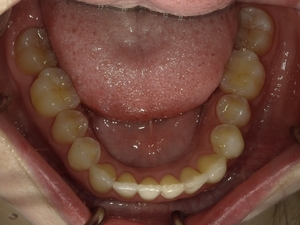

ガタガタとした歯並びや八重歯(叢生)CASE66